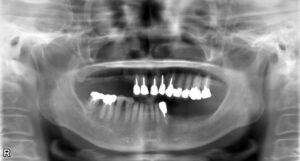

下顎大臼歯2本欠損症例

BEFORE AFTER 44歳男性/下2本/インプラント埋込手術 【治療内容】 左右の第二大臼歯の炎症が大きく、抜歯と…